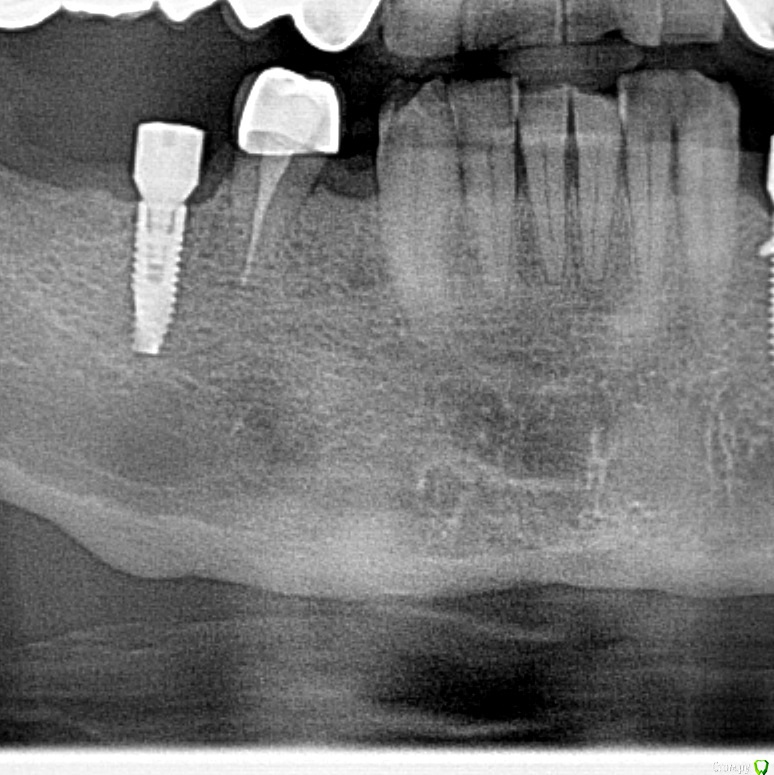

wladdX Опубликовано 6 мая, 2020 Поделиться Опубликовано 6 мая, 2020 (изменено) Мне тоже кажется, что вы принимаете балочную структуру и петли н\ч канала за н\образование. Такое встречается иногда. Похожий случай На ОПТГ выглядит уже не так трагично Изменено 6 мая, 2020 пользователем wladdX 1 Ссылка на комментарий

Fin Опубликовано 7 мая, 2020 Автор Поделиться Опубликовано 7 мая, 2020 Мне тоже кажется, что вы принимаете балочную структуру и петли н\ч канала за н\образование. Такое встречается иногда. Похожий случай46_1.jpg На ОПТГ выглядит уже не так трагичноОПТГ фрагмент.jpgЧестно говоря тоже думаю, что костный рисунок но смутили размеры и то что в других местах кроме этих таких явлений не наблюдается. Сейчас пациент предоставил снимок до ортод. лечения. На нем немного видно костный рисунок. Ссылка на комментарий